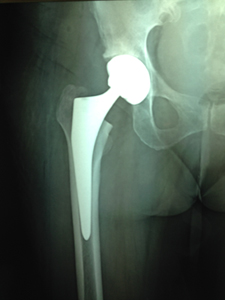

ΑΡΘΡΟΠΛΑΣΤΙΚΗ ΙΣΧΙΟΥ

Τεχνική AMIS: Η πολύ μικρή πρόσθια προσπέλαση του ισχίου υπερτερεί επειδή είναι ατραυματική (δεν υπάρχει διατομή μυών ή τενόντων) όπως συμβαίνει στις υπόλοιπες τεχνικές. Η τεχνική αυτή με το ειδικό εξάρτημα χειρισμού του σκέλους με την πολύ μικρή τομή επιτυγχάνει καλό οπτικό πεδίο προσπέλασης. Σπάνια χρειάζεται μετάγγιση αίματος, η νοσηλεία είναι σύντομη (1-2 ημέρες) ενώ η βάδιση με μερική φόρτιση είναι άμεση. Ο πόνος είναι ελάχιστος και στο μεγαλύτερο αριθμό των ασθενών ανεπαίσθητος.

| Προεγχειρητική | Μετεγχειρητική |